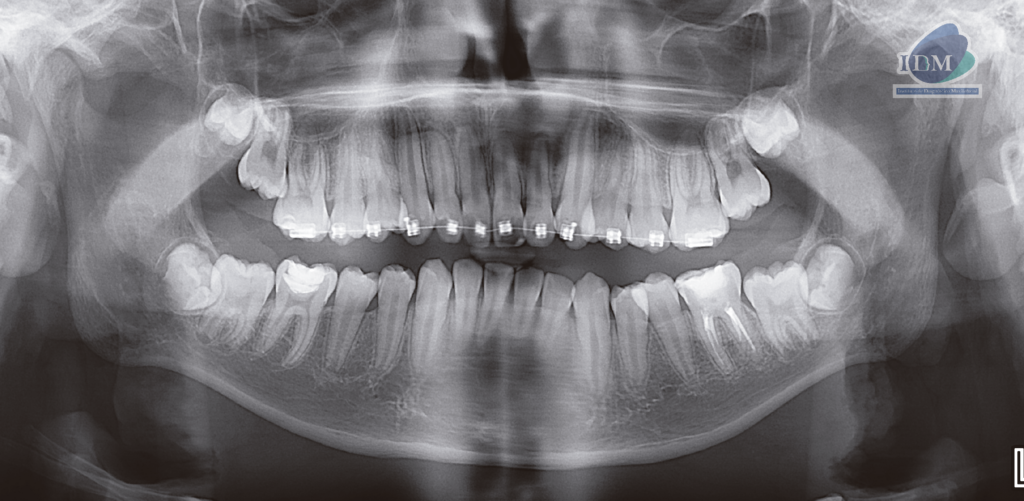

En la radiografía panorámica (Figura 1), se aprecia mineralización segmentada de los procesos estilohioideos, apartotologia fija de ortodoncia en maxilar superior, pieza 36 presenta restauracion oclusal y obturación de conductos, pieza 46 restauracion oclusal.

Radiografia Panorámica